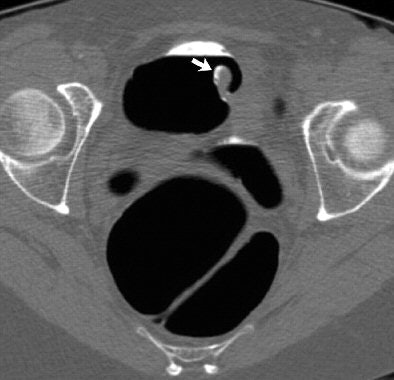

| Inverted appendiceal stump in 63-year-old asymptomatic woman referred to CT colonography (CTC) for routine colorectal cancer screening. Three-dimensional endoluminal view from prone CTC dataset shows discrete 10-mm pedunculated polypoid lesion located at medial aspect of cecal tip. Image republished with permission of the American Roentgen Ray Society (AJR 2006; 186:535-538). |

The patient described above was referred for routine colorectal screening with VC. Her surgical history was significant only for remote appendectomy. She underwent standard bowel preparation of oral sodium phosphate (45 mL), 2% barium sulfate suspension (250 mL), and water-soluble iodinated contrast material (diatrizoate, 60 mL) the day before the exam.

Supine and prone CT images were acquired on a MDCT scanner (LightSpeed Ultra, GE Healthcare, Chalfont St. Giles, U.K.) using an 8 x 1.25 detector configuration, 1-mm reconstruction interval, 120 kVp, and 50 mAs. The study was interpreted by an experienced gastrointestinal radiologist using V3D Colon software (Viatronix, Stony Brook, NY). Primary 3D interpretation with 2D correlation of suspicious findings was used to interpret the results.

CT findings revealed a 10-mm pedunculated polypoid lesion at the medial base of the cecum. No additional findings were identified, but despite the surgical history and location of the lesion, "a neoplastic polyp could not be confidently excluded," the authors wrote. The patient was referred for conventional colonoscopy, which was negative.

"The endoscopic appearance of the polypoid cecal lesion was thought to be most compatible with an inverted appendiceal stump," the authors wrote. Biopsies revealed benign colonic mucosa with underlying lymphoid tissue.